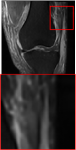

Public Dataset. The public dataset employed is the FastMRI Knee [43], where the reference contrast is PD, and the target contrast is FS-PD. We selected 1600 slices with a training, validation, and test set split ratio of 7:1:2.

Figure 5 provides the qualitative comparison of the various methods on the four datasets at a scale of 4. The top, second, third, and bottom rows are the SR results under the FastMRI, clinical brain, clinical tumor and clinical pelvic datasets, respectively. The red boxes indicate the zoom-in region of complicated anatomical structures along with their corresponding error maps. Note that the brighter textures in the error maps, the lower the quality of the reconstructed images. As can be seen, compared to methods based on Transformers and CNNs, diffusion-based methods like DisC-Diff and DiffMSR (Ours) are capable of reconstructing high-realistic images with promising reconstruction metric scores (PSNR and SSIM). Nevertheless, while DisC-Diff can reconstruct high-precision MR images, it does not preserve the structure present in the original HR images, introducing some additional information that can affect medical diagnosis. In contrast, our method combines DM and PLWformer, which can preserve the original image’s structure while restoring high-frequency information.

In this section, we present more visual qualitative comparisons. Figures 8, 9, 10, and 11 show the reconstruction results of each method in FastMRI, clinical brain, clinical tumor, and clinical pelvic, respectively. As can be seen, although DisC-Diff can reconstruct MR images with high-frequency information, it fails to preserve the structure and content of the original Target HR image effectively, resulting in image distortion. In contrast, our proposed DiffMSR can restore high-frequency information while preserving the structure of the original HR image, indicating the effectiveness of the joint use of DM and PLWformer.